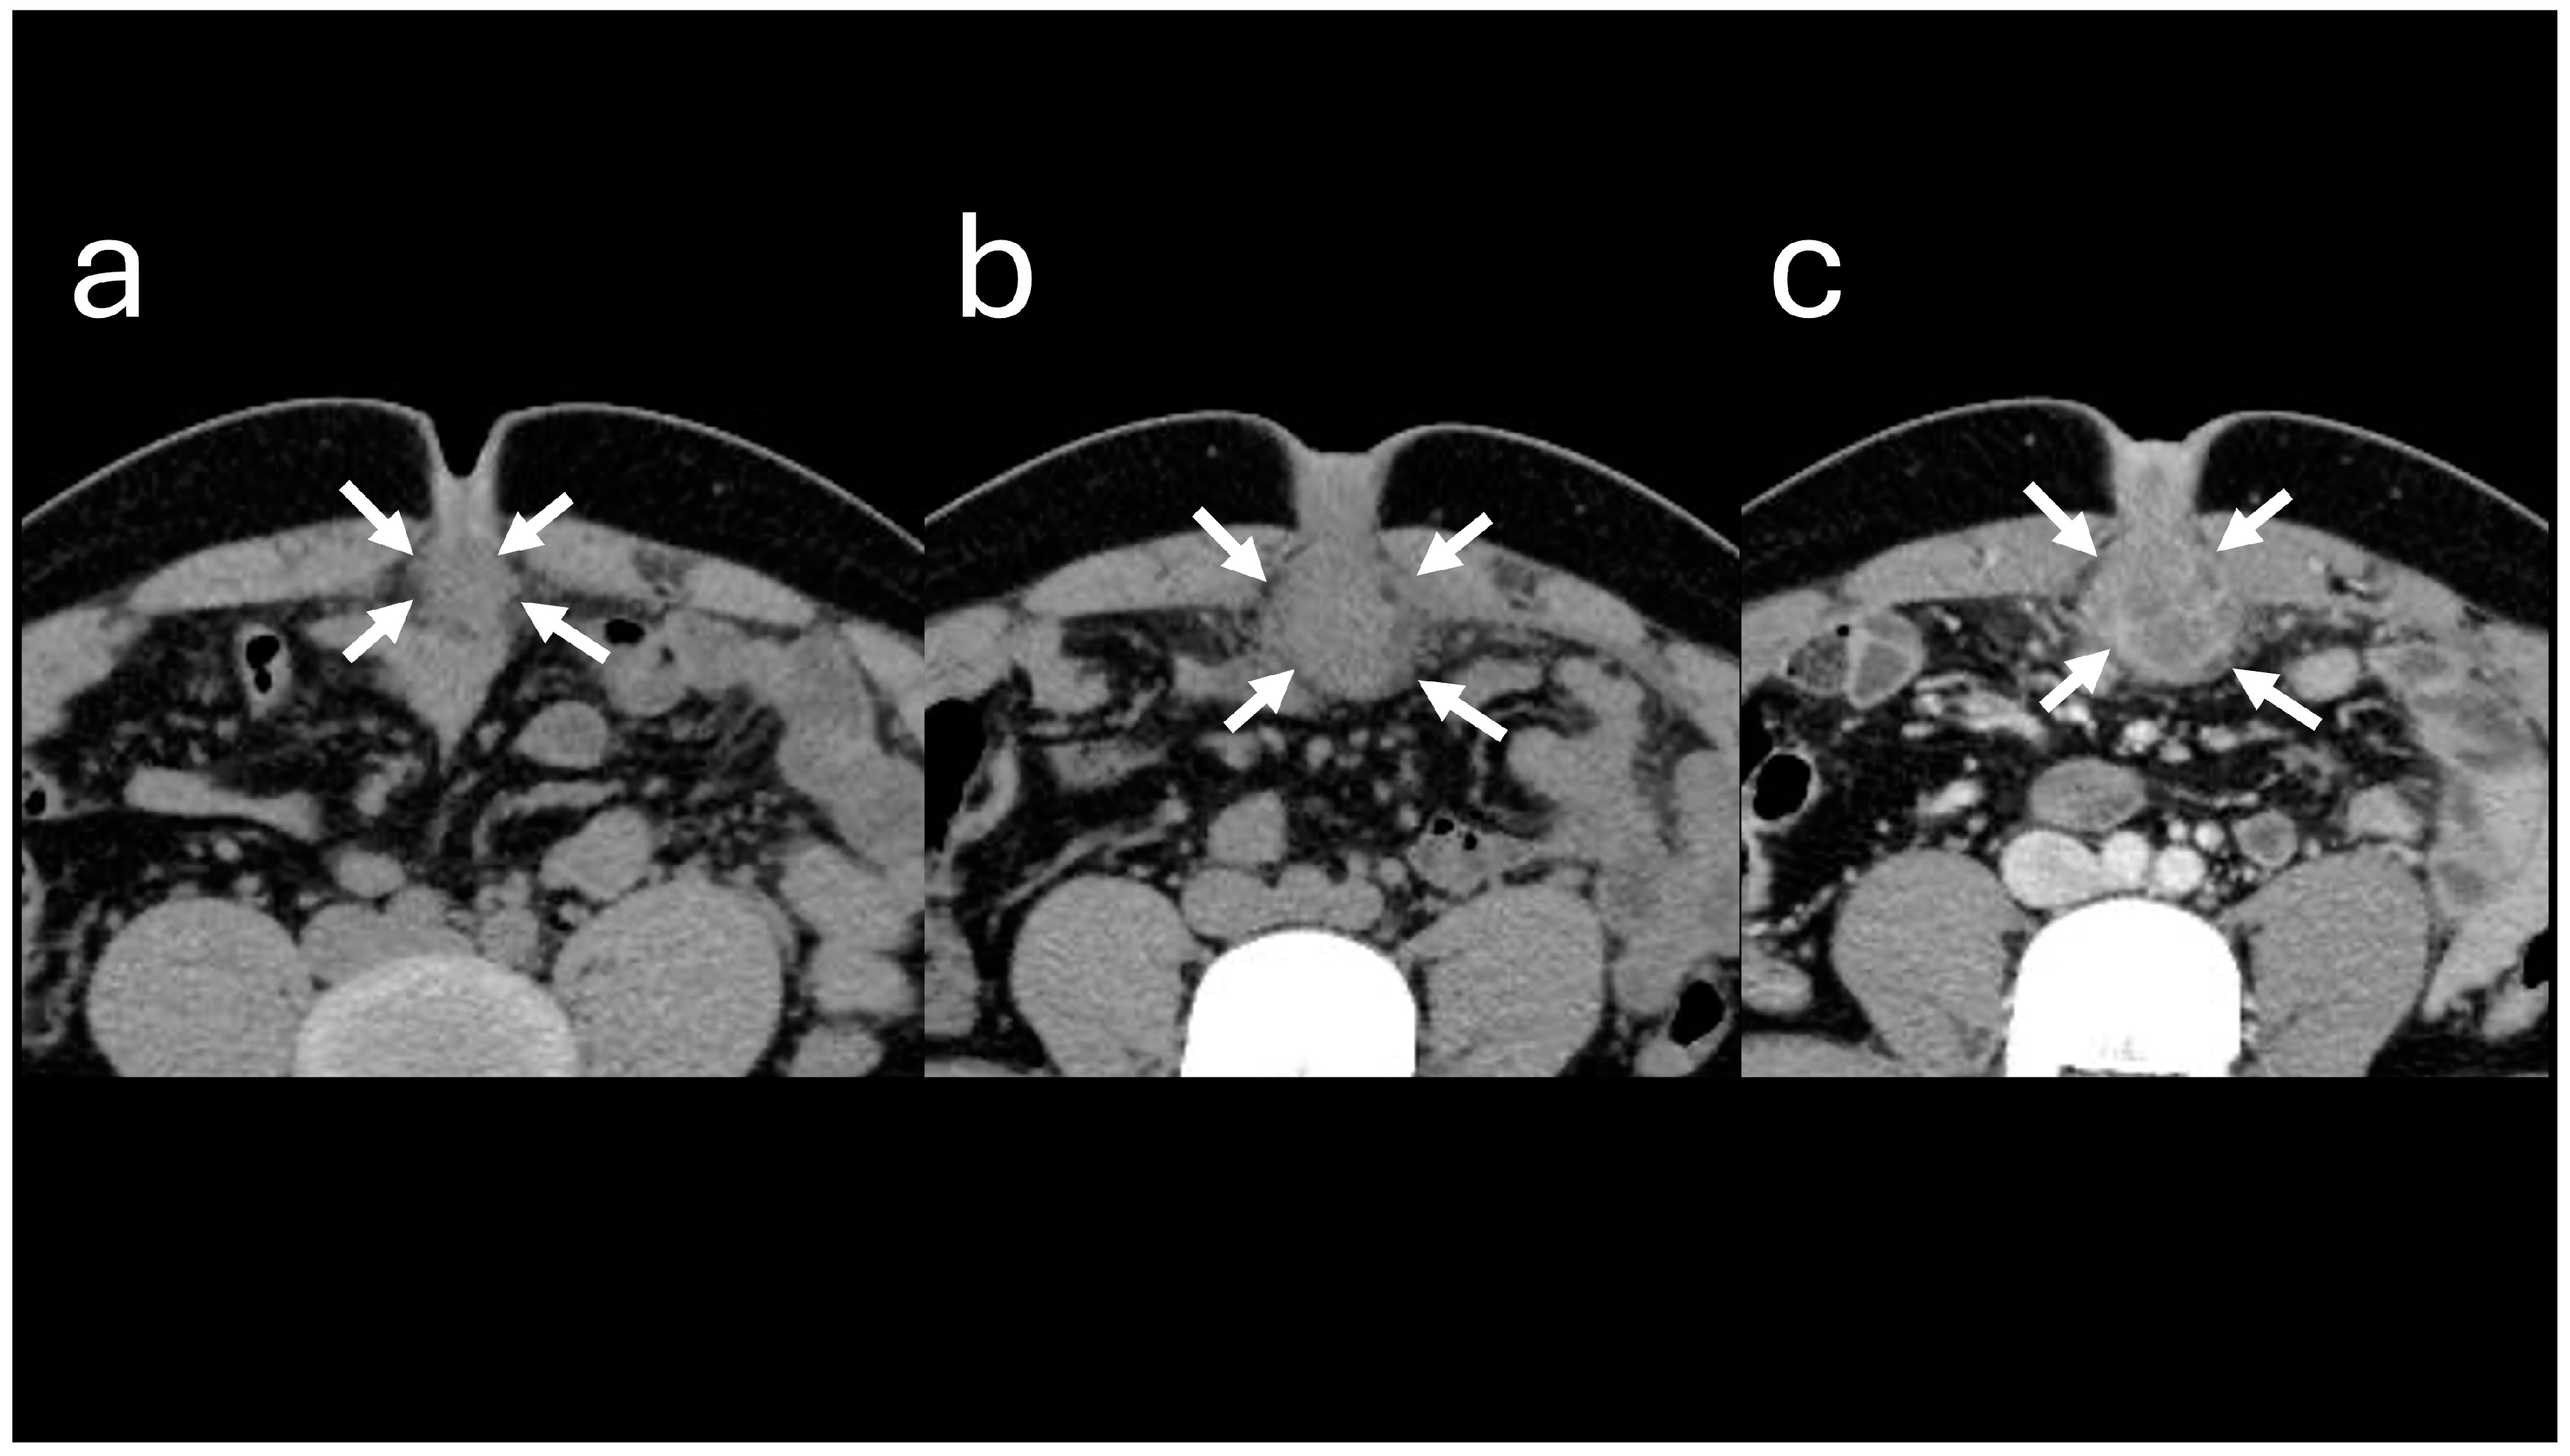

The A-US and A-CT findings suggested the enlargement of the abscess below the umbilicus. Enhanced A-CT revealed multilocular abscesses (Figure 4 and Figure 5). The abscess was drained with the patient under sedation, with local anesthesia administered as follows: intravenous midazolam (3 mg), intravenous pentazocine (15 mg), and subcutaneous injection of lidocaine (8 mg). When the base of the umbilicus was opened with mosquito forceps, a large amount of purulent discharge was observed (Figure 6). The umbilicus was carefully washed, and a drainage tube was inserted at its base. The Gram stain of the pus showed a multi-bacterial pattern including Gram-positive cocci, Gram-positive rods, and Gram-negative rods (Figure 7). He was hospitalized at our hospital, and the oral antibiotic was changed to intravenous ampicillin/sulbactam (3 g every 8 h).

Figure 5. Abdominal computed tomography images. (a) Image obtained at the time of initial visit. (b) Image obtained at the time of the second visit. The soft tissue lesion below the umbilicus (indicated by arrows) appears enlarged. (c) Contrast-enhanced image demonstrates a multicapsulated soft tissue lesion.